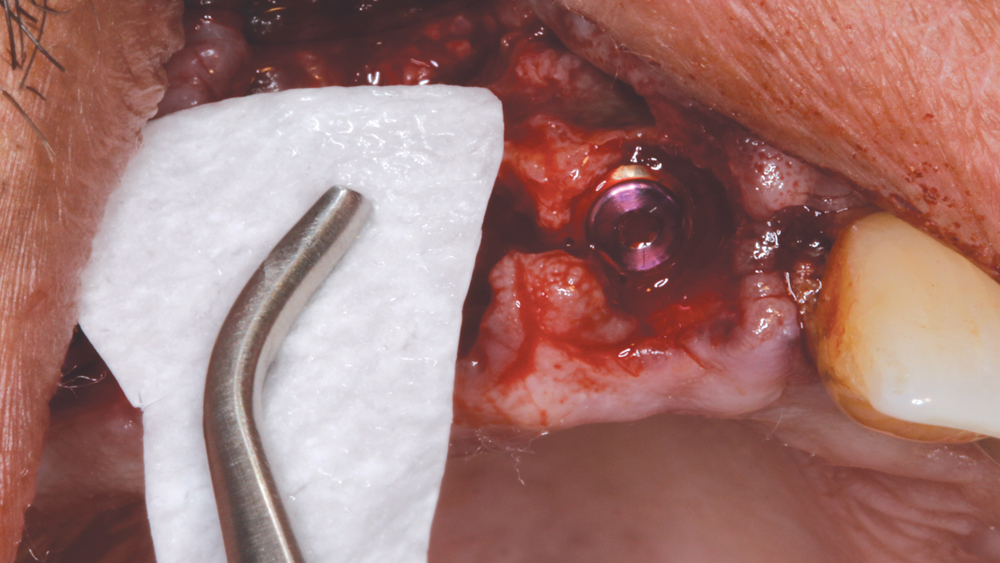

After removing the untreatable teeth, I placed five Hahn Tapered Implants into the extraction sockets, grafted the area with Newport Biologics™ Mineralized Cortico/Cancellous Allograft Blend (Glidewell Direct) mixed with harvested autograft from the osteotomy sites, and used a Newport Biologics Resorbable Collagen Membrane 3-4 (Glidewell Direct) as a barrier against epithelial downgrowth during the healing and remodeling phase.

The Hahn™ Tapered Implant (Glidewell Direct; Irvine, Calif.) was ideal for this case because it has a pronounced thread design, a machined collar for soft-tissue maintenance, and a prosthetic connection that facilitates platform switching, which serves to preserve bone and gingival tissue around the implant-abutment interface.

Ideal Implant Selection and Grafting of the Site

The Hahn™ Tapered Implant was chosen for Weldon because it is ideally suited for this type of case. For example, the pronounced threads excel in establishing initial implant stability in a fresh socket site. The machined collar helps to prevent bone loss around the neck of the implant and also has a cleansable surface. The prosthetic connection with built-in platform-switching helps to minimize the resorption that could occur with other systems, where the connection between the implant and abutment is at bone level, by preventing a microgap and potential bacterial invagination. And of course, the Hahn Tapered Implant System allows for either a cemented or screw-retained restoration.